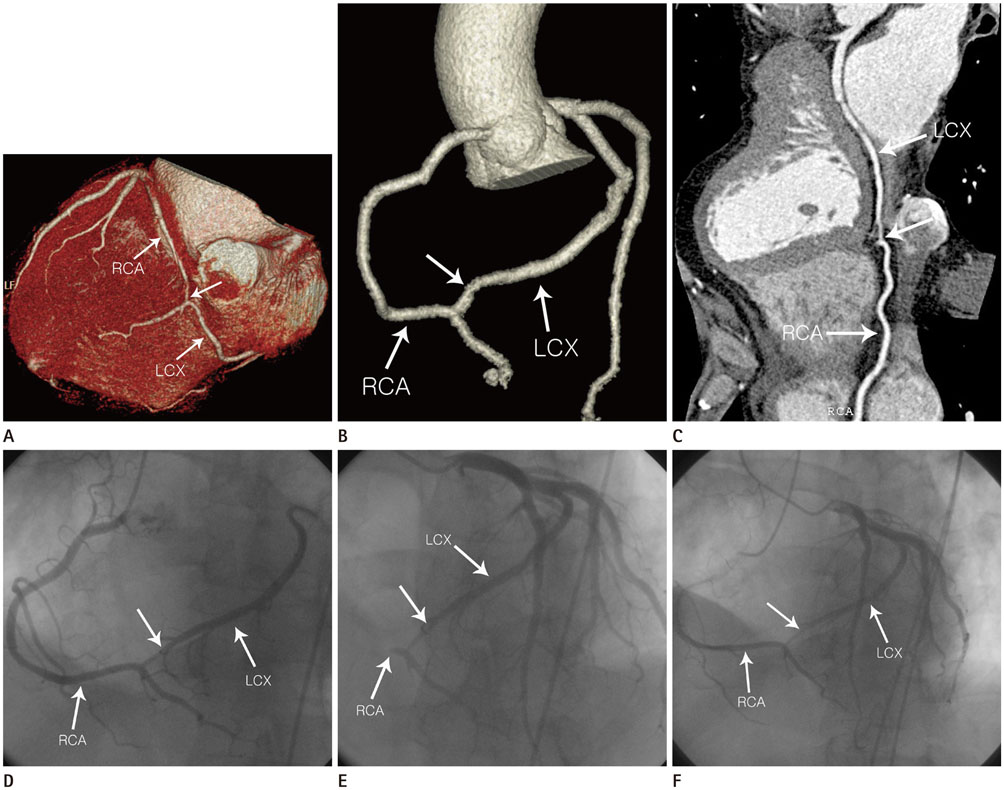

Communication between the Right and Circumflex Coronary Arteries Discovered Incidentally by Multidetector Computed Tomography

Intercoronary communication is a rare congenital coronary anomaly. We present a case of a 48-year-old man with an incidentally discovered communication between the right and circumflex coronary arteries, who was admitted with chest tightness and exertional dyspnea. The initial diagnosis was made using electrocardiogram-gated multidetector computed tomography.